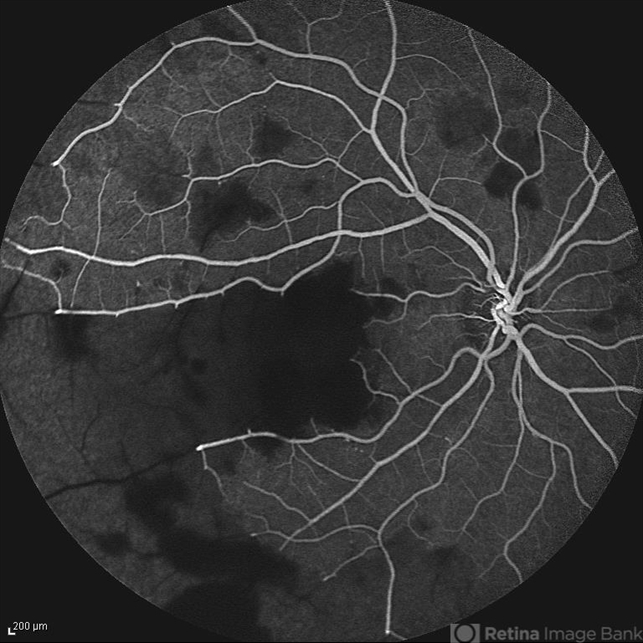

- retinal vasculitis, capillary nonperfusion

- Mid phase fluorescein angiogram of the right eye of a 28-year-old woman with acute drop of vision due to occlusive retinal vasculitis leading to extensive capillary nonperfusion and macular infarction.